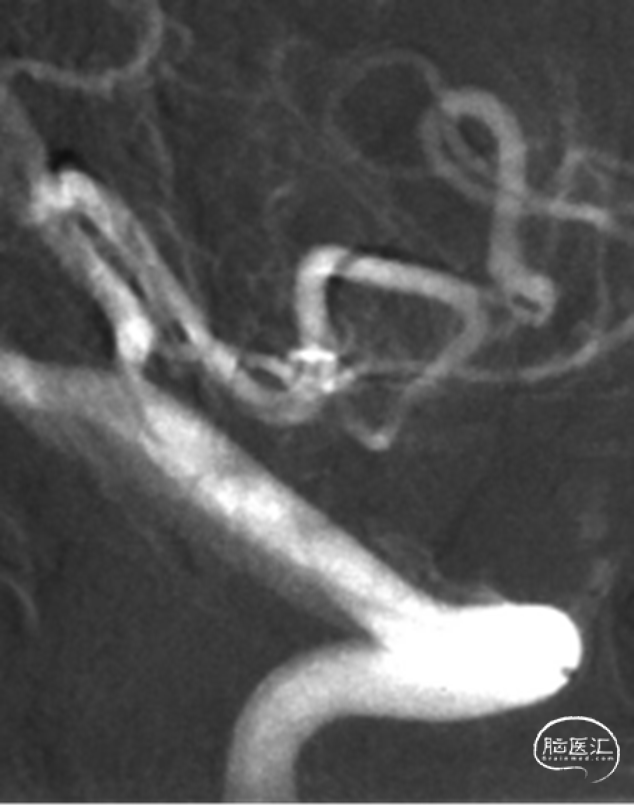

入院急诊DSA提示右侧小脑后下动脉远端动脉瘤,动脉瘤位于PICA蚓部分支

二维及三维重建提示动脉瘤形态不规则,可见瘤壁存在小泡凸起,瘤颈宽3.6mm,瘤高2.0mm,瘤体最大径2.5mm,未见血管明显痉挛

行单纯弹簧圈栓塞及载瘤动脉闭塞术。术后即刻造影提示动脉瘤不显影,载瘤动脉闭塞,侧枝代偿良好